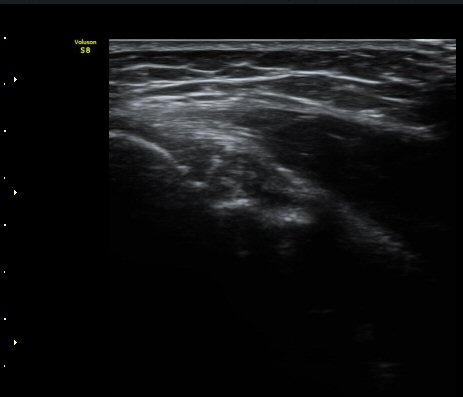

³»»ó°ú Á¾´Ü¸é°Ë»ç»ó  ³»ÃøºÎÀδë Àú¿¡ÄÚ ºÎÁ¾°ú ³»»ó°ú ÀÎ´ë ºÎÂøºÎ ÇÇÁú°ñÀÇ ºÒ±ÔÄ¢º¯È­¿Í

°ñÆíÀÌ °üÂûµÇ°í(±×¸² 1, 2, 3, 4) ÀÌ·±¼Ò°ßÀº °ÇÃø°ú ºñ±³ÇÏ¸é ´õ¿í ¶Ñ·ÈÇÔ(±×¸² 5, 6).